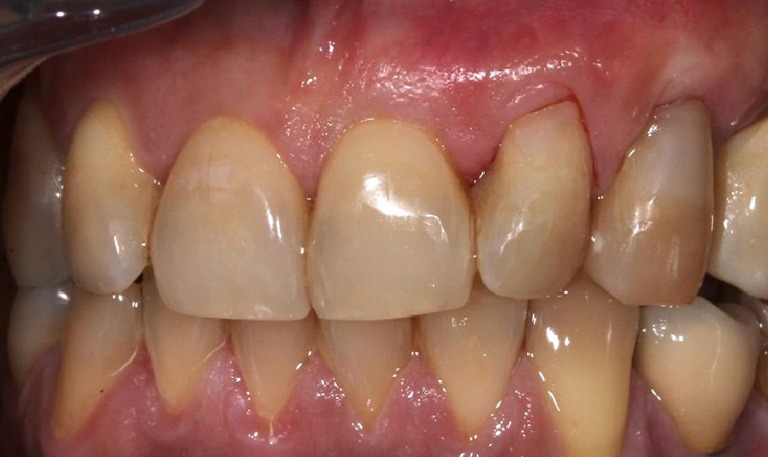

Injerto de encía para solucionar recesión

BeforeAfter